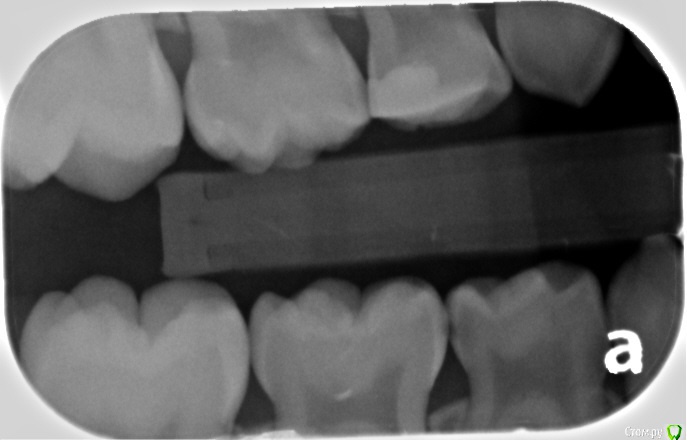

Два фото январских и одно от апреля прошлого года (где четверка еще с пломбой).

В первую очередь интересует верхняя левая четверка - в ней разрушилась пломба и часть зуба, сейчас стоит временная полимерная пломба. Есть варант удалить и поставить расширитель, но будет ли хорошей идеей поставить сейчас коронку, или это безнадежно? Сколько она сможет простоять?

Также интересуют остальные потенциальные пломбы/коронки (нам собираются ставить как минимум одну коронку и три пломбы).